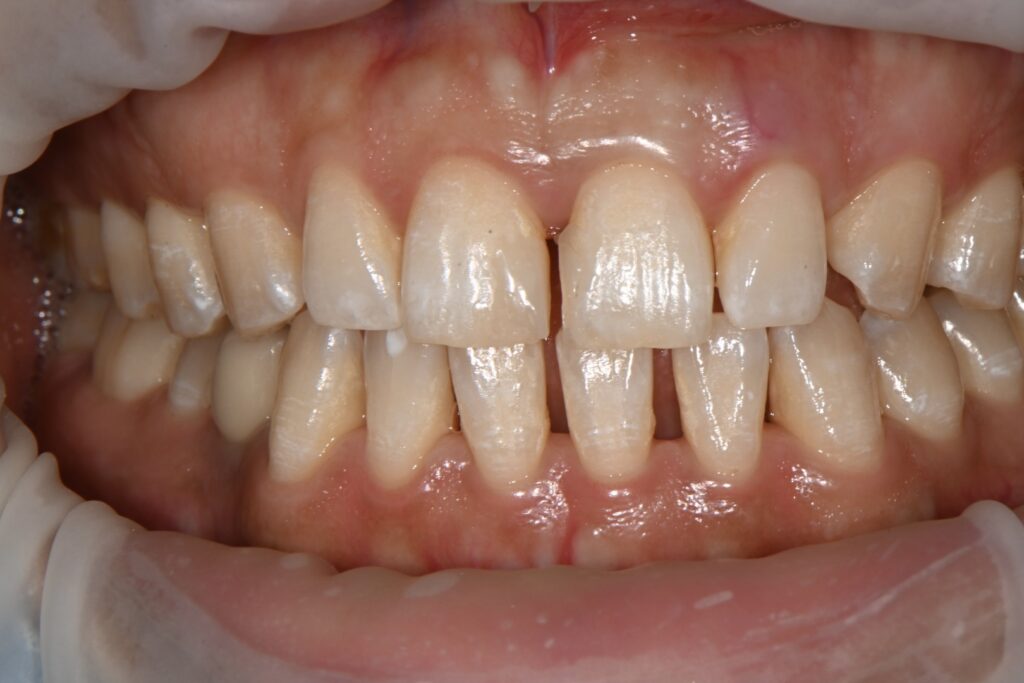

몇년전에 앞니를 레진으로 하셨다는 분이 내원하셨습니다

전형적인 잘못된 레진 입니다

1.모양 2.변색 3.파절 모든 레진의 부작용이 일아나고 있네요